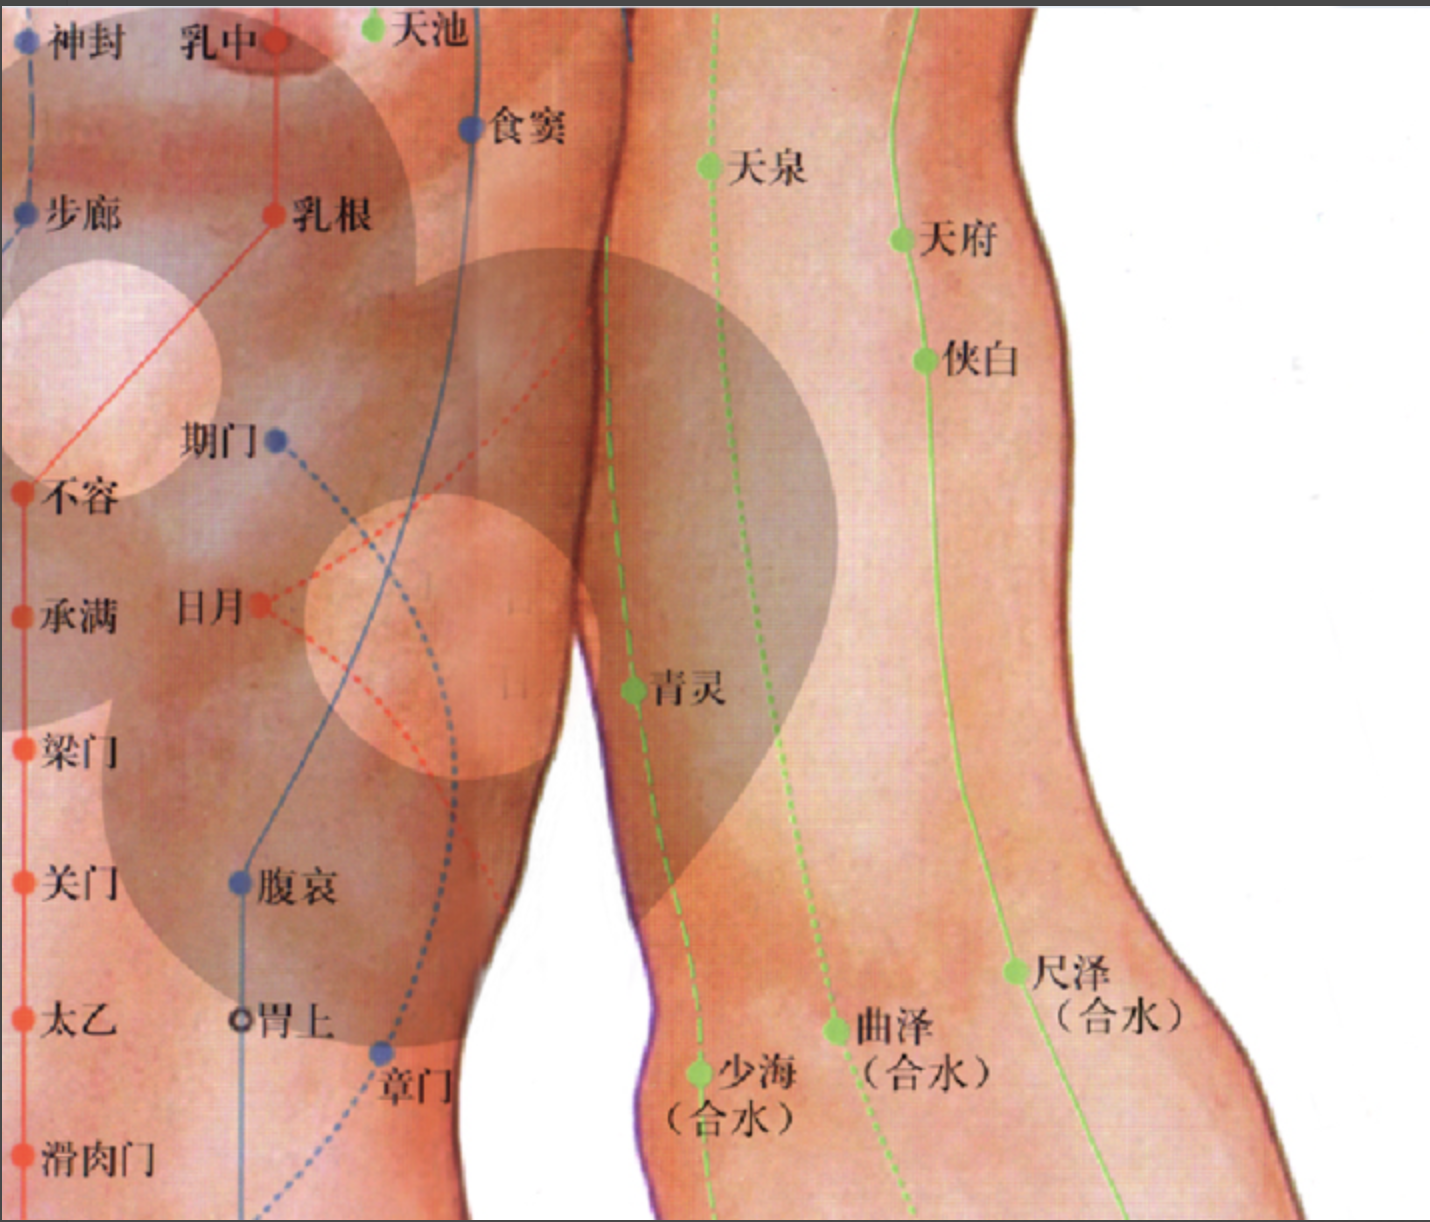

【(九)手厥阴心包经(图 10-27-1)】

2、歌诀 九穴心包手厥阴,天池天泉曲泽深,郄(xì)门间使内关对,大陵劳宫中冲侵。

3、经脉循行 起于胸中,出属心包络,向下通膈,从胸至腹依次联络上、中、下三焦。

胸部支脉:沿胸中,出于胁肋至腋下(天池),上行至腋窝中,沿上臂内侧行于手太阴和手少阴经之间,经肘窝下行于前臂中间进入掌中,沿中指到指端(中冲)。

掌中支脉:从劳宫分出,沿无名指到指端(关冲),与手少阳三焦经相接。

4、主要病候 心痛、胸闷、心惊、心烦、癫狂、腋肿、肘臂挛痛、掌心发热等。

5、主治概要 主治心、胸、胃、神志病及经脉循行部位的其他病证。